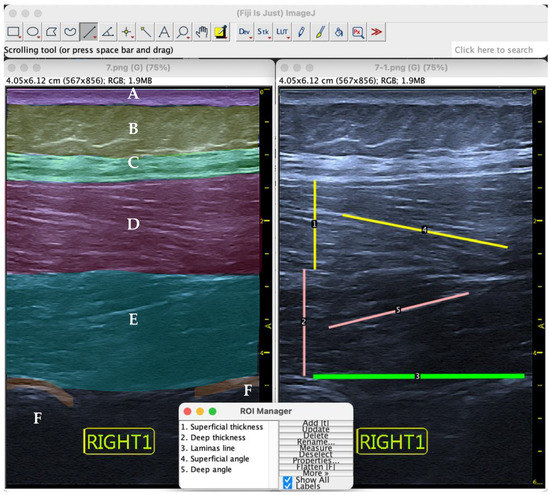

Procedure